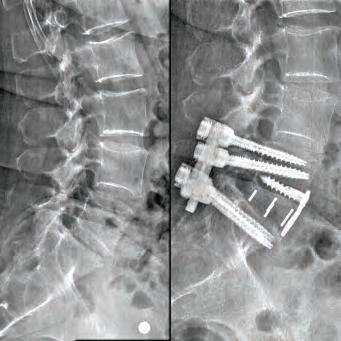

Led by Dr. Courtney, the skilled team at Advanced Spine Center cares for patients with neck and back pain using a wide array of the most state-of-the-art tools and techniques—from conservative physical therapy and injection therapy—to advanced pain manage-

SPINE SURGEON PRACTICING FOR 28 YEARS.

ment, as well as surgical intervention. We employ the latest in minimally invasive spine surgeries, in addition to cutting-edge replacement technology. Incorporating both high tech and high touch, we get our valued patients back to their lives so they can enjoy all the activities they love.

SURGERY: L5/S1 360° LUMBAR FUSION

SURGERY: L4/5, L5/S1 360° LUMBAR FUSION